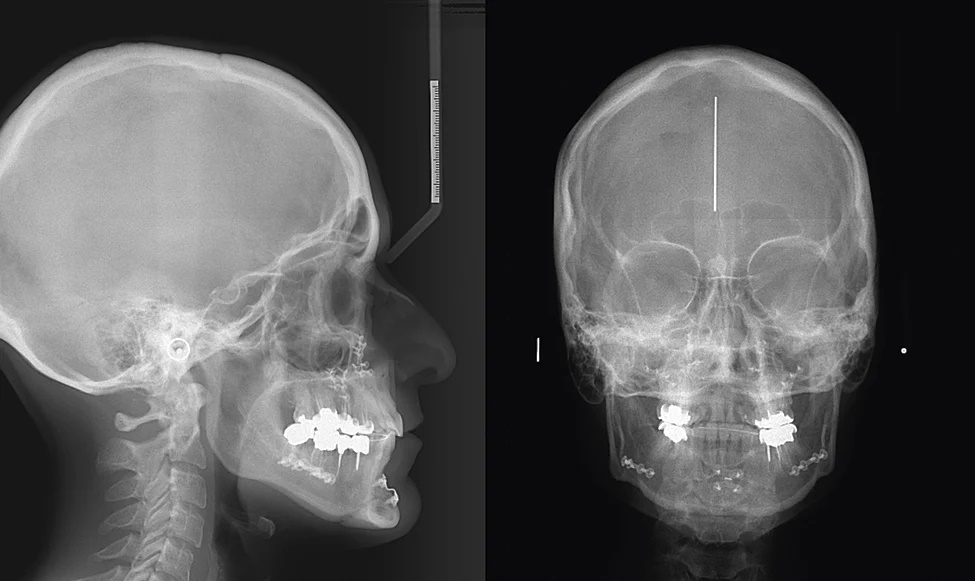

Основные режимы цефалостата — съемка в боковой (латеральной) и прямой (фронтальной) проекции. По снимку в боковой проекции врач определяет угол наклона челюстей, тип прикуса, перспективы роста челюстно-лицевых структур, старые травмы лицевых костей и зубочелюстной системы. Особенно информативны латеральные ТРГ при лечении тяжелых аномалий прикуса. Например, когда ортодонту приходится двигать зубы функциональными аппаратами или несъемными конструкциями сразу в трех плоскостях. В этих случаях в процессе лечения делают несколько ТРГ в боковой проекции, чтобы держать на контроле инклинацию резцов и вовремя корректировать положение ортодонтических конструкций.

Снимки в прямой передне-задней проекции делаются со стороны лица и затылка. Этот вид ТРГ тоже преимущественно ортодонтический: позволяет увидеть анатомические особенности зубных рядов, оценить аномалии окклюзии, тип и степень лицевой асимметрии. В последние годы набирает тренд антивозрастная стоматология и именно фронтальные проекции ТРГ помогают идентифицировать среднюю линию и оценить потенциал лифтинга нижней трети лица за счет коррекции возрастных изменений зубочелюстной системы.tomograf5.jpg